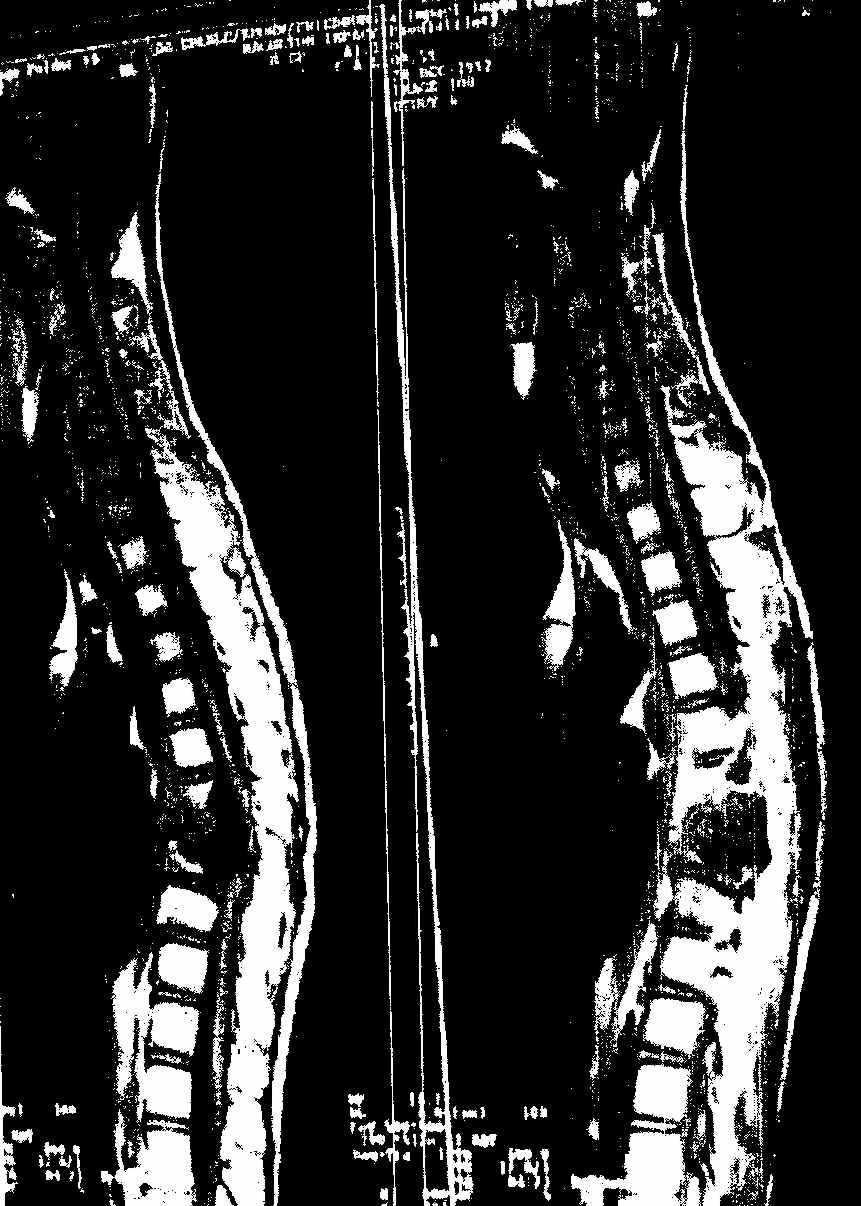

Магнитно-резонансную томографию позвоночного столба выполняют в сагиттальной и аксиальной плоскостях. Она дает возможность продемонстрировать позвоночный столб и спинной мозг на большой длине без введения в субарахноидальное пространство контрастных веществ. На магнитно-резонансных томограммах шейного отдела позвоночного столба в аксиальной проекции тела позвонков имеют квадратную форму. Назад от тел позвонков отходят дуги с отростками, хорошо видны отверстия, через которые проходит позвоночная артерия. Тела поперечных отростков пояснично-крестцового отдела массивные, величина их увеличивается от I до V позвонков (рис. 6.3-6.5).

На магнитно-резонансных томограммах четко обозначаются мягкие ткани позвоночного столба, спинной мозг, межпозвоночные диски и связки. При этом четко высвечиваются контуры спинного мозга и его положение в позвоночном канале.

| Рис. 6.3. Магнитно-резонансная томограмма грудного отдела позвоночного столба. Место деструкция 10 и 11 грудных позвонков с компрессией спинного мозга. | |

| Рис. 6.5. Магнитно-резонансная томограмма пояснично-крестцового отдела позвоночного столба в сагиттальной плоскости. | Рис. 6.4. Магнитно-резонансная томограмма шейного отдела позвоночного столба в сагиттальной плоскости. |